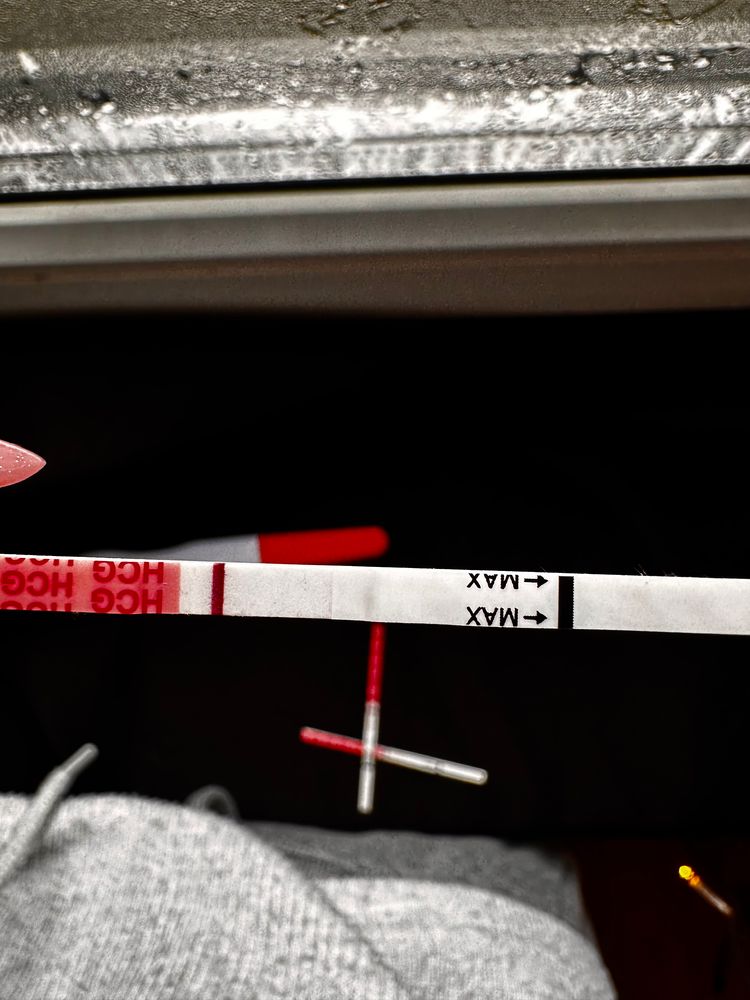

Девачки, почитала всех и короче пошла тесто манить , не могу уснуть теперь 😂😂😂😂 во что получилось напоминаю на 6 дпо

тест на о сегодняшний

Тест с верху старый 2 цикла назад

Тест с верху старый 2 цикла назад

Тест с верху старый 2 цикла назад

Тест с верху старый 2 цикла назад

у меня в беременность именно тесты на овуляцию показали жирные // , сделала тест на б и была еле заметная полоска . Сейчас прикреплю . Но к сожалению замерла на 6 Нед